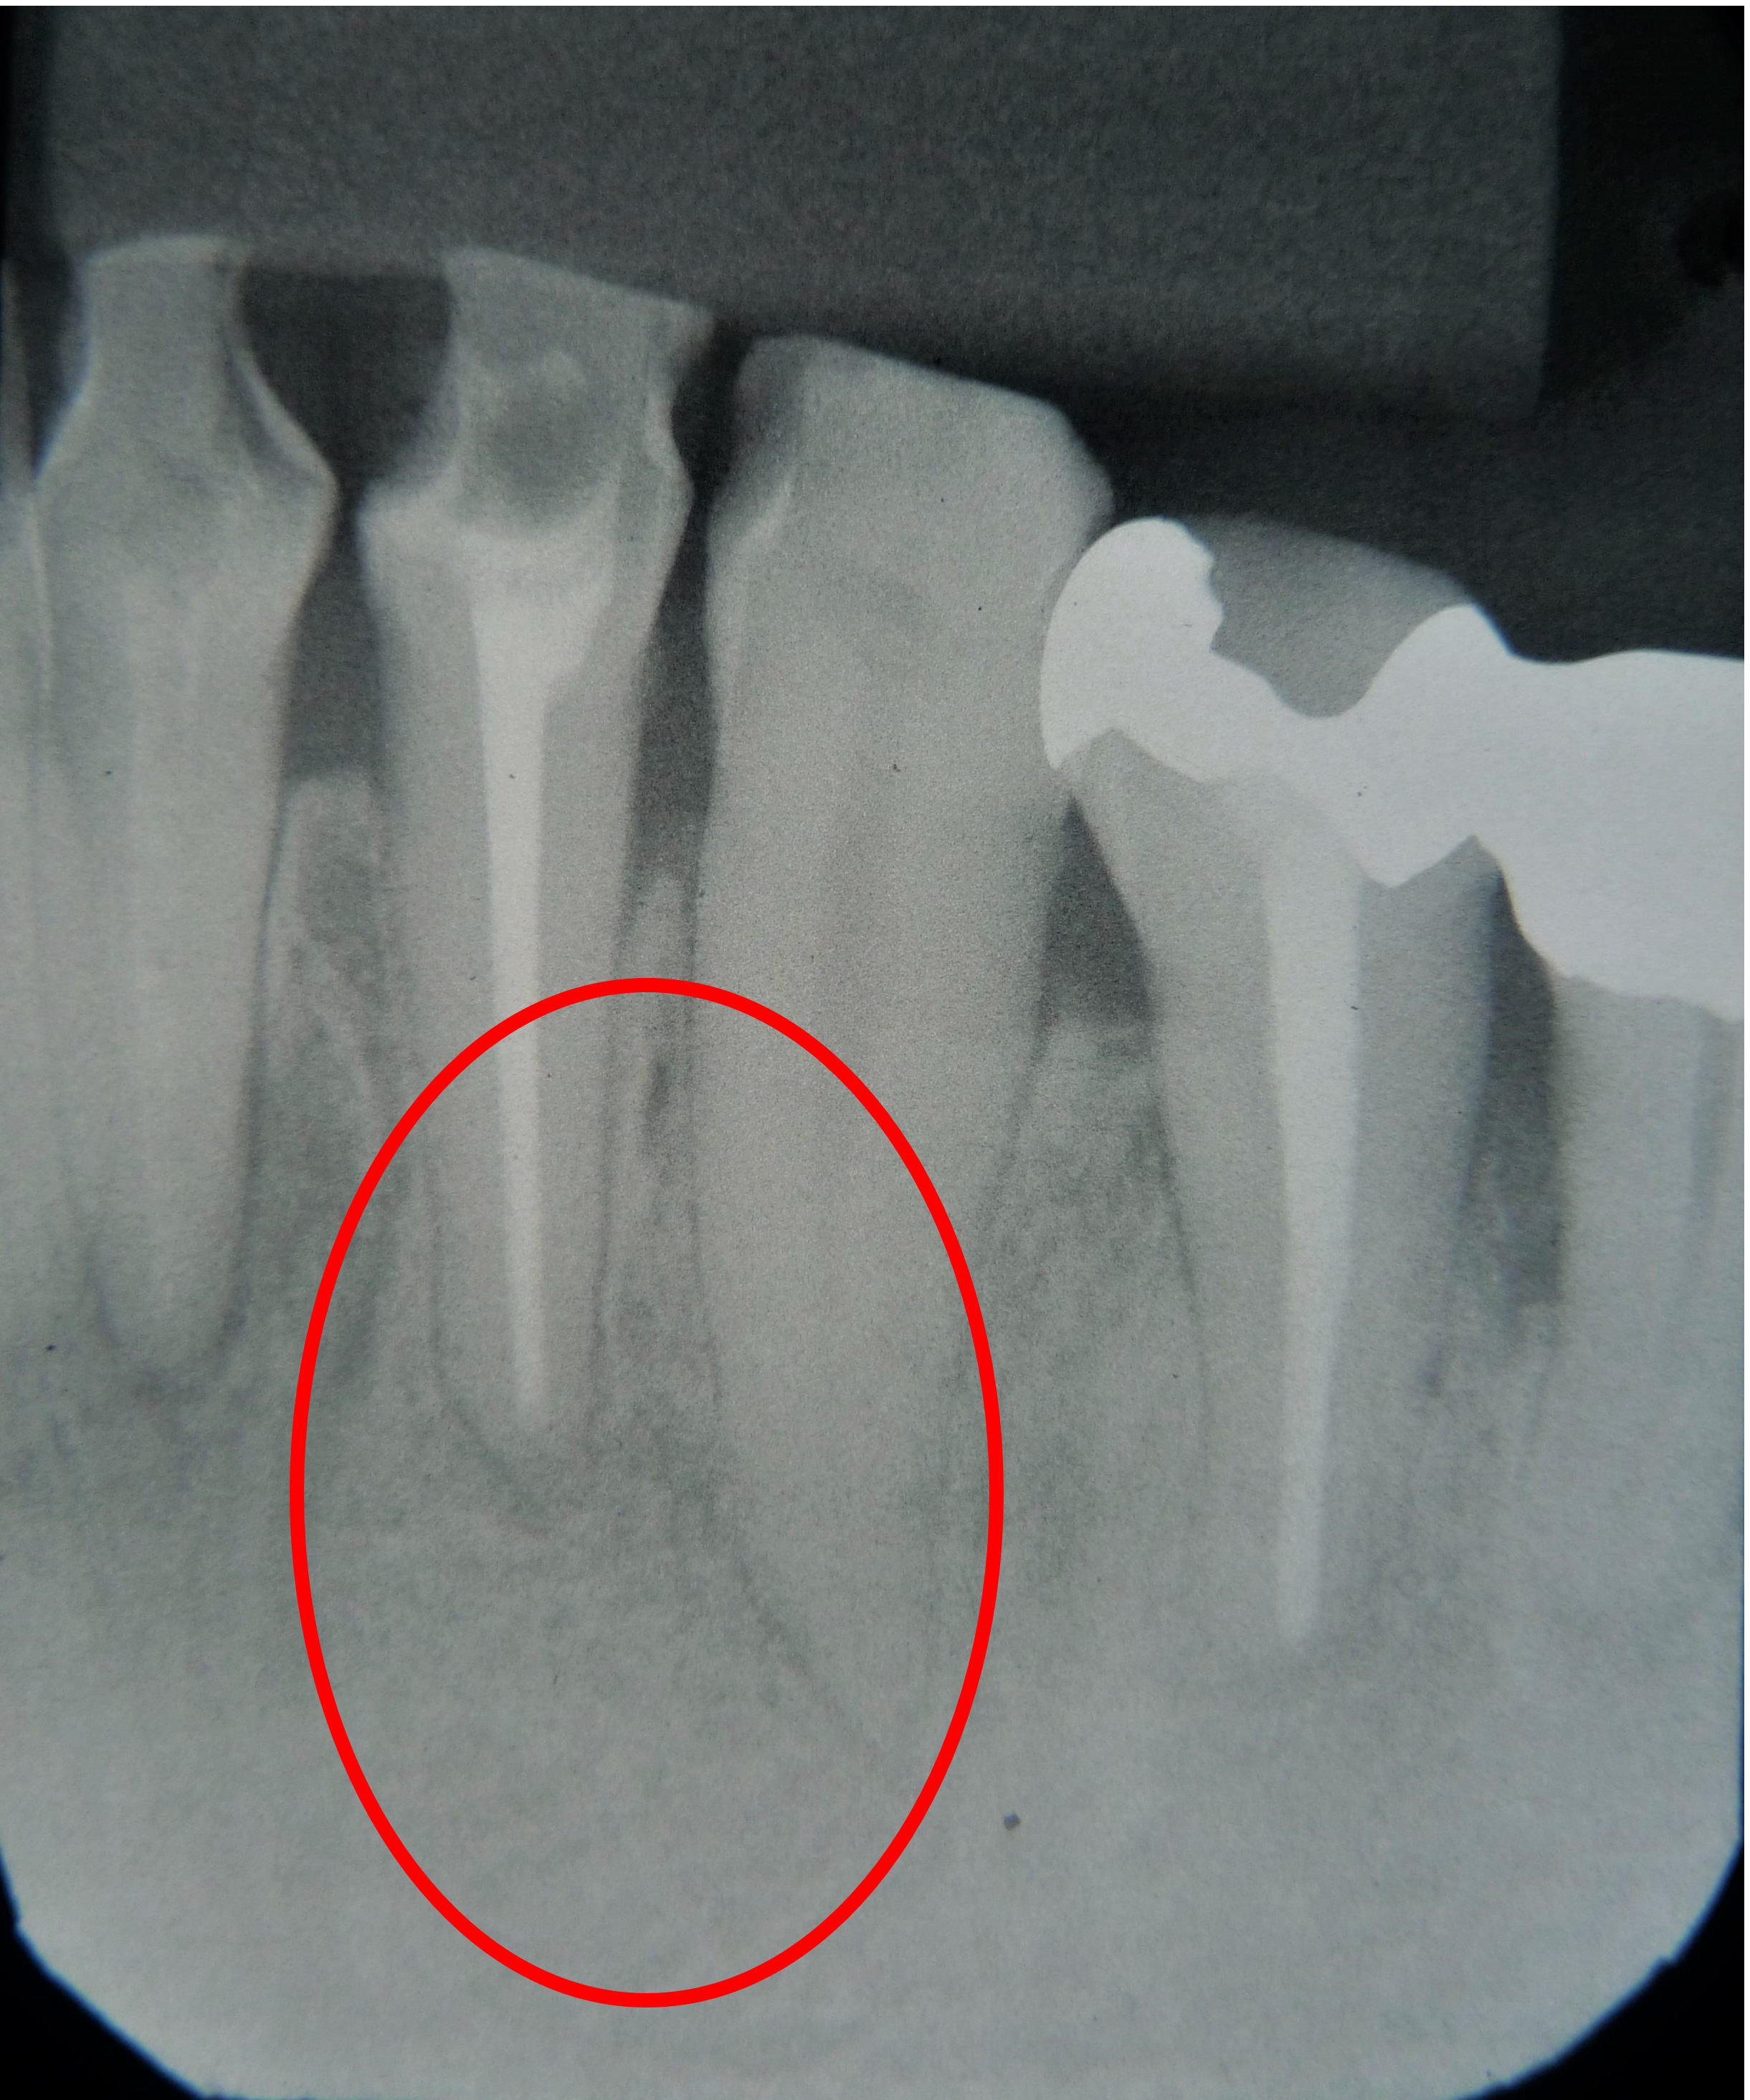

レントゲンで黒い部分が大きいので

手術をしました。

術後わずかに黒い名残がありますが、

黒い部分はほとんどなくなりました。

根の中をきちんと清掃しても化膿が治らないことがまれにあります。また一度治ったように思えて

も再発してしまうこともあります。

このような時は手術をして膿を取り除く必要があります。

また化膿の範囲が大きい場合(レントゲンで直径2cm以上)は最初から手術の適応になります。